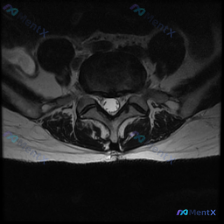

今天整理了一份只有单张腰椎MRI T2加权轴位片的椎间盘病变分析案例,跟大家分享一下读片和临床分析的思路。 病例影像基本信息 本次仅提供单张腰椎MRI T2加权轴位图像,具体读片发现如下: 1. 节段定位:根据椎体、椎弓根和关节突形态判断,该切面位于腰椎,最可能为L4/5或L5/S1水平 2. 椎间...

看到这一份腰椎MRI读片病例,临床怀疑存在椎间盘病变,我们整理一下影像资料和完整分析思路,大家一起讨论。 病例影像资料 本次提供的是腰椎MRI T2序列轴位图像,分析如下: 1. 扫描层面:位于下腰椎节段,可清晰辨认中央的硬膜囊、马尾神经根,以及侧方的关节突关节、椎旁肌肉 2. 核心影像发现: -...

这是一份单张腰椎MRI T2轴位影像的分析病例,核心问题是:临床怀疑椎间盘病变,影像上能看到什么问题?整理了完整的读片和分析思路分享给大家。 一、影像基本信息 本次提供的是腰椎MRI T2序列轴位单一层面图像,定位为腰椎椎间盘层面,我们按结构逐一读片: 1. 骨性结构与韧带:椎体形态、骨皮质连续,无...